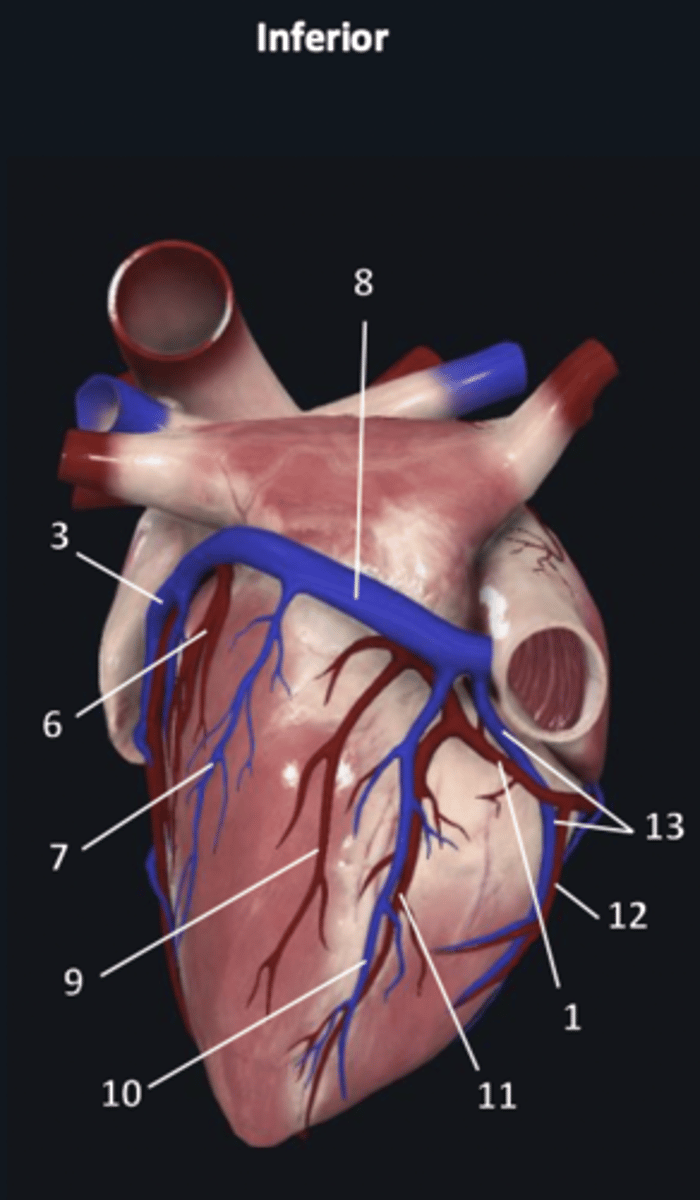

right coronary artery

1

great cardiac vein

3 (blue)

coronary sinus

8

right coronary artery

1 (red)

great cardiac vein

3

posterior left ventricular artery

6

posterior vein of left ventricle

7

coronary sinus

8

right posterolateral artery

9

middle cardiac vein

10

posterior interventricular artery

11

right marginal artery

12

small cardiac vein

13